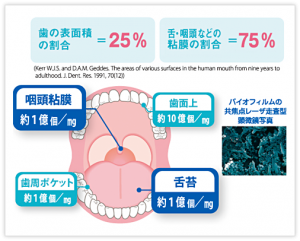

口腔細菌は歯の表面だけでなく、舌の上、咽頭などの粘膜にも多く存在します。

毎日のホームケアでは歯磨きだけでなく、歯と歯の間や粘膜のケアも行いましょう。

①歯磨き・・・歯に付着した歯垢や汚れを落とします

②フロスや歯間ブラシ・・・歯ブラシの届かない歯間や歯と歯茎の境目の歯垢を除去します

③マウスウォッシュ・・・お口や咽頭を殺菌します

この3ステップをしっかりお家で行なって頂くことでリスクを軽減することができます。

うがい、手洗いはもちろんですが、ぜひお口のケアもお忘れなく😊